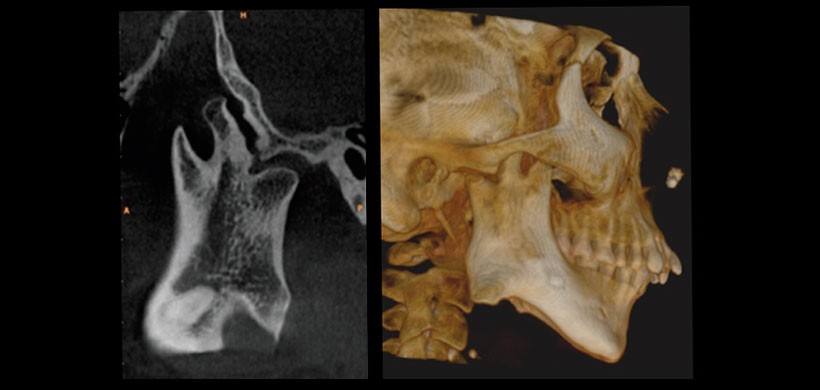

Debido a la superposición de imágenes, se optó por la exploración mediante la tomografía volumétrica de haz cónico, específicamente para determinar la morfología exacta de la ATM derecha. En la cual se observó una proyección ósea de aproximadamente 16,5 mm de la escotadura sigmoidea, la cual se extiende en sentido anterosuperior a una distancia de 6,9 mm de la apófisis coronoides y 12,1 mm del cóndilo mandibular. Y en la reconstrucción 3D se aprecia de manera ilustrativa esta alteración ósea a nivel de la escotadura sigmoidea de lado derecho. [Figura- 4].

Figura 4: Cone Beam – Reconstrucción multiplanar y renderizado 3D